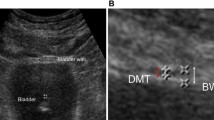

In all, 56 adult female Sprague–Dawley rats were equally randomized into seven groups: normal control group, and 4w, 6w, 8w, 10w, 12w and 16w groups after medullary cone injury, assigned as groups A–G. The model was established by sharp transaction of spinal cord at the level of L4/5 vertebral body. Bladder weight, cross-sectional area and ultrastructure of the detrusor muscle and its neuromuscular junction (NMJ), fibrotic change, and α-smooth muscle antibody (α-SMA) expression in the detrusor muscle were examined individually.

Bladder weight in groups E–G was significantly increased than that in group A (P<0.05). And cross-sectional area of detrusor muscle fiber in groups E–G was significantly smaller than that in group A (P<0.05). Transmission electronic microscopy showed that the number of synaptic vesicles, mitochondria and other organelles in NMJ decreased markedly in group E. In groups F and G, NMJ further degenerated with synaptic vesicles and organelles decreased or even disappeared. Masson's stain showed that the proportion of connective tissue in the detrusor muscle of groups E–G was significantly different from that of group A (P<0.05). α-SMA expression in the detrusor muscle decreased with the lapse of time.